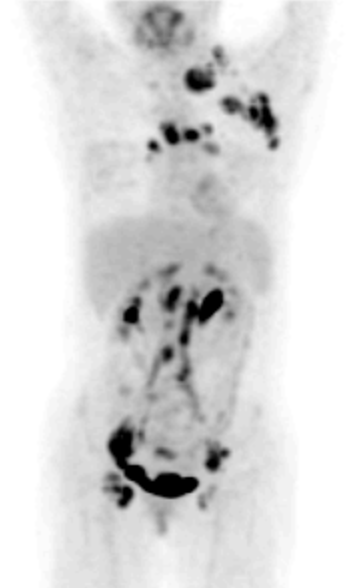

72세 여성이 오른쪽 목 부위에 만져지는 덩어리를 호소하며 병원을 방문했다. 5년 전에 자궁경부암으로 진단받고 항암화학방사선요법을 시행한 후 추적관찰 중이었다. 덩어리 부위에 실시한 세침흡입검사 결과, 편평상피세포암으로 확인되었다. 아래는 혈액검사 결과와 양전자방출단층촬영술(PET-CT) 이미지이다. 적절한 치료 방법은 무엇인가?

• SCC 종양표지자 수치 증가, 세침흡입검사 상 편평상피암, PET-CT 상 자궁경부를 포함한 전신에서의 uptake 소견으로 자궁경부암의 재발 및 원격 전이를 진단할 수 있다.